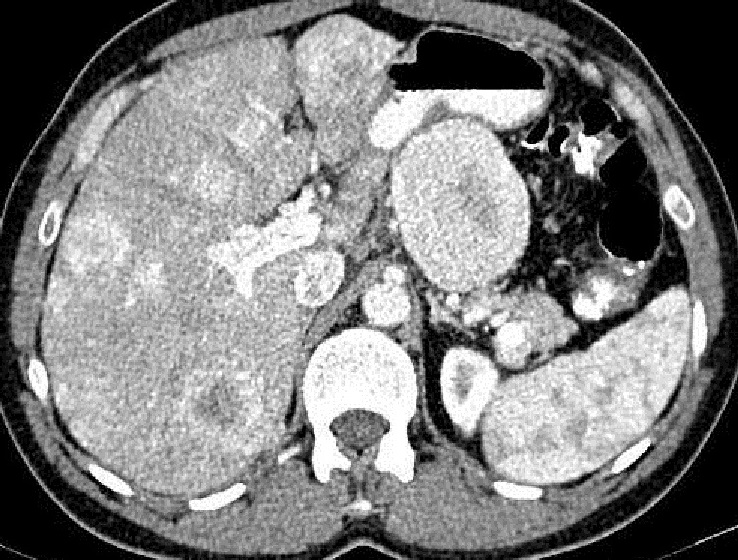

Image radiologique TDM plus C +

d'un tumeur endocrine non fontionelle du pancreas

avec des nodules metastasique du foie . Aspect

hypervascularise hyperdense avec zone necrose

parenchymateuse hypodense central se voyait tres

nette . Coupe radiologique TDM axiale avec contrast

intraveineuse au phase arterielle |

Meme cas en coupe

TDM coronale |